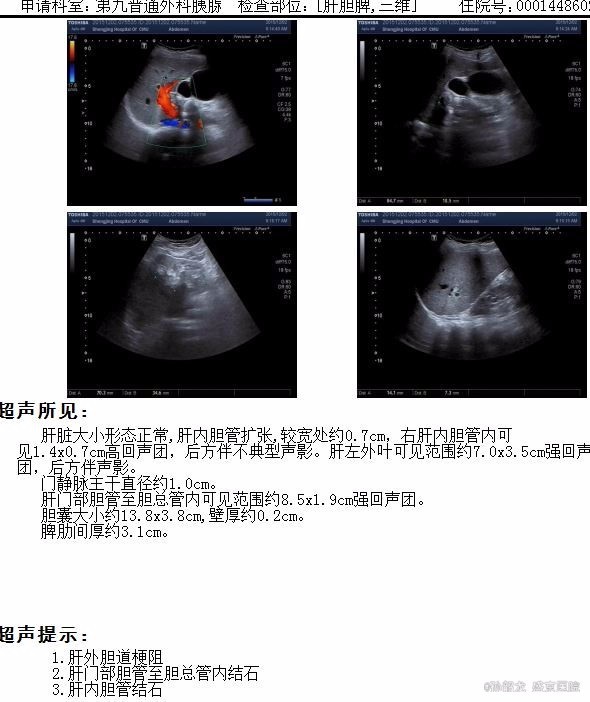

查体:全身皮肤及巩膜无黄染,腹软不胀,未见胃肠型及蠕动波,全腹平软,全腹无压痛及无反跳痛,无肌紧张,Murphy's征(-),肝区叩痛(-),双肾区叩击痛(-),移动性浊音(-),肠鸣音6次/分。 辅查: 肝功能化验,总胆红素及直接胆红素正常,转氨酶有升高。 MRCP提示胆囊增大,肝内外胆道内多发结石,伴胆道梗阻。 腹部BUS提示 1.肝外胆道梗阻, 2.肝门部胆管至胆总管内结石, 3.肝内胆管结石。